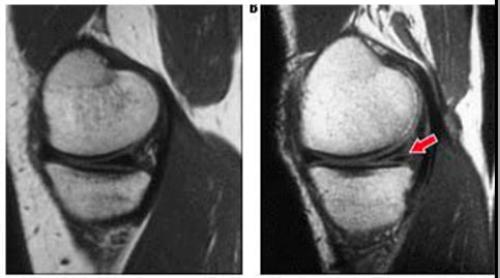

Степень повреждений мениска определяют посредством МРТ.

Чтобы в заключениях не было расхождений, врачи всего мира ориентируются на диагностические признаки состояния мениска по Столлеру (Stoller, американский ортопед, разработавший систему оценки):

Различные степени повреждения мениска по Столлеру. Нажмите на фото для увеличения